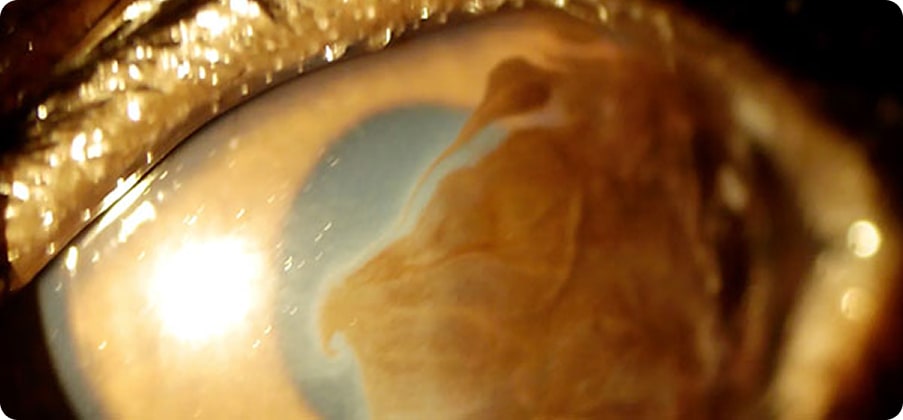

免疫異常による角膜・強膜の炎症と腫脹が特徴の病気です。コリーやシェルティ、コッカーに好発しますがあらゆる犬種で発生します。